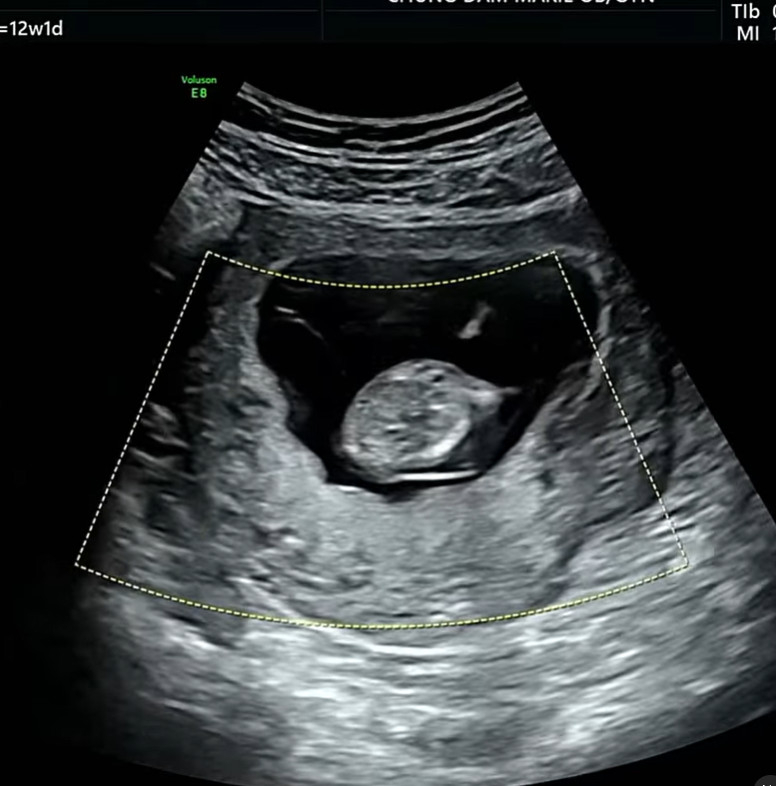

유튜버 심리섭과 결혼한 배우 배슬기가 임신 12주차 초음파 영상을 공개했다.

배슬기는 17일 자신의 인스타그램에 "올봄은 원 없이 꽃놀이했다. 마지막은 신난 우리 리슬이 12주차 초음파. 날 닮았나 아주 흥이 많아 가만히를 안 있네"라고 말했다.

그는 임신 12주차 초음파 영상도 함께 공개했다. 아기가 신났는지 이리저리 움직이는 모습을 보여 이목을 끌었다.